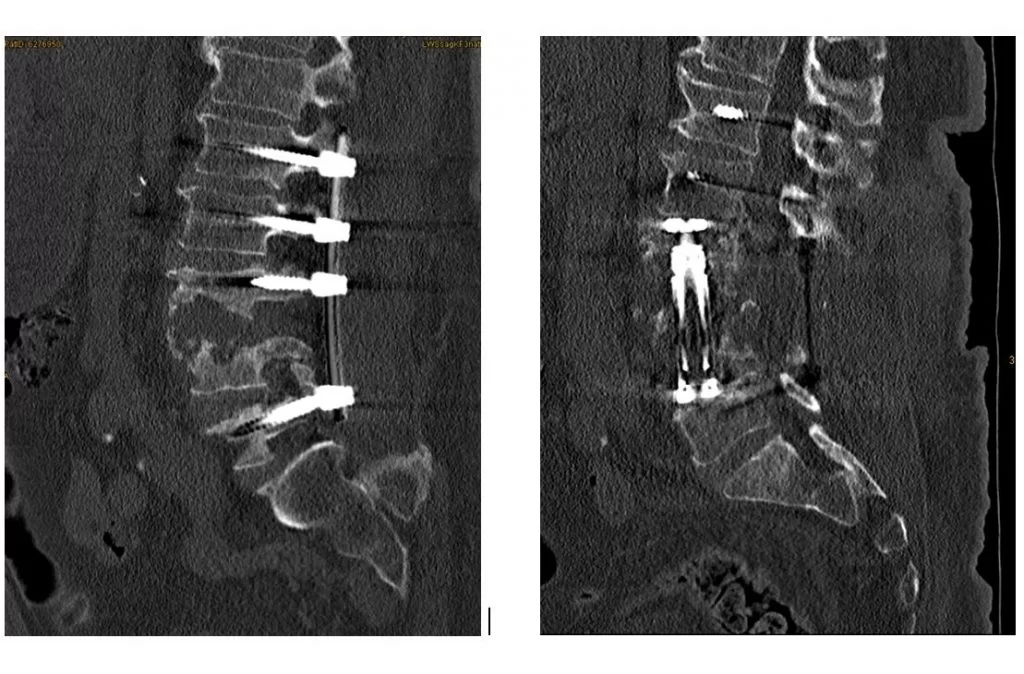

- Νεοπλασία ή φλεγμονή: όταν ένας σπόνδυλος έχει προσβληθεί απο νεοπλασία ή φλεγμονή (σπονδυλοδισκίτιδα), (Εικόνα 2) και πρέπει να αφαιρεθεί.